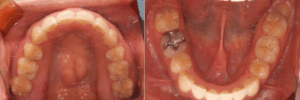

before

〈年齢・性別〉20代 女性

〈診断名〉上顎前歯前突

〈装置〉インビザラインコンプリヘンシブ

〈抜歯部位〉上下顎左右4

〈治療期間〉2年6か月